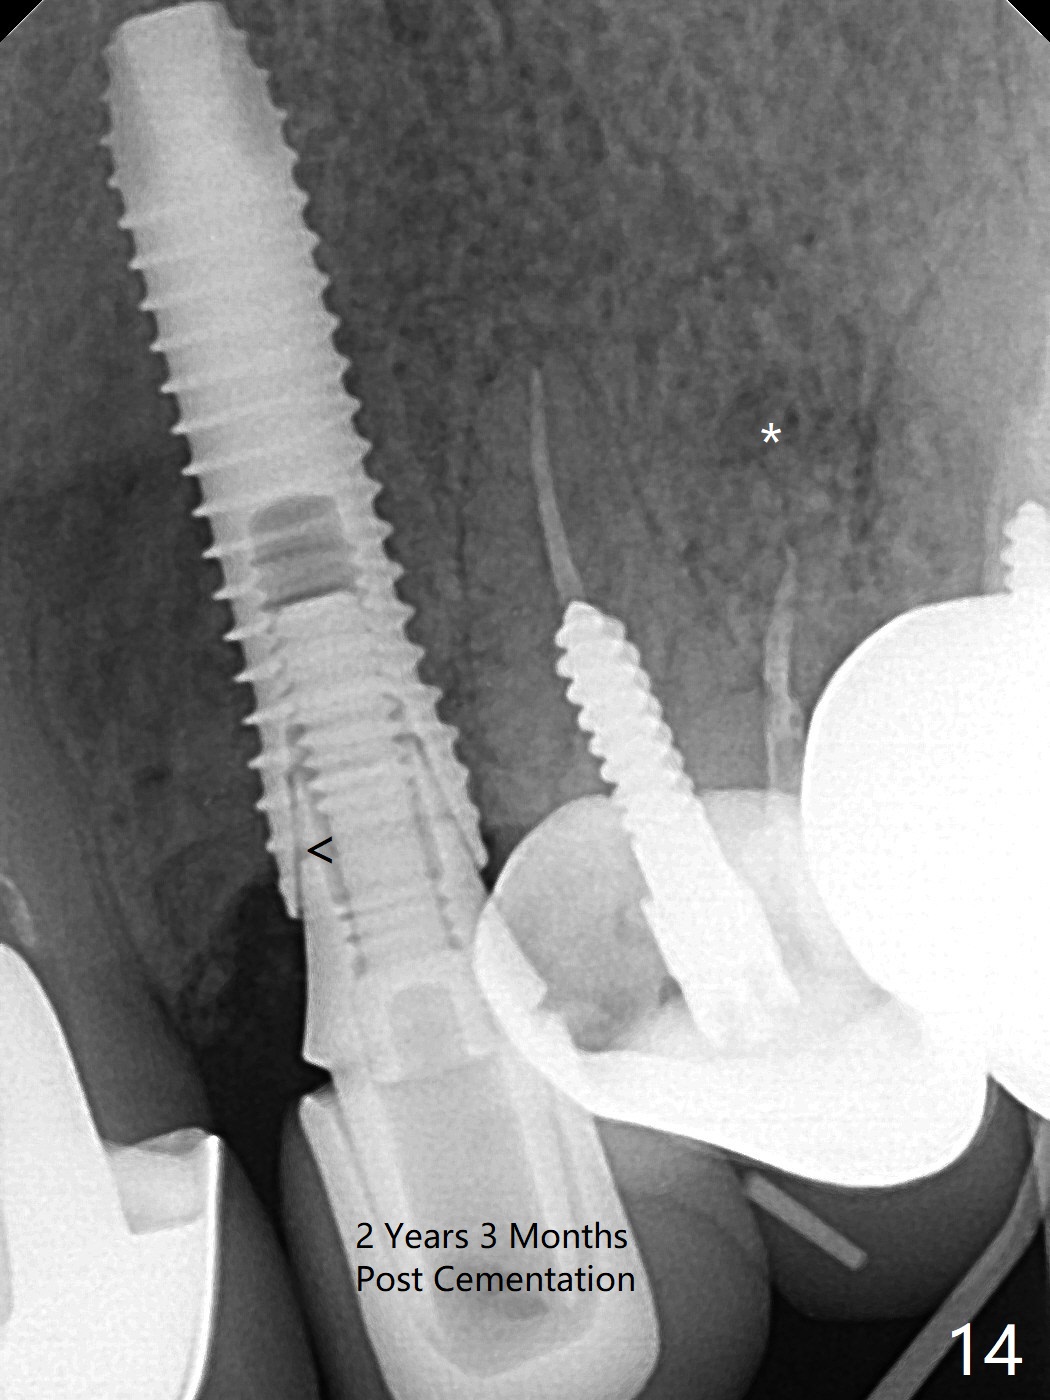

In spite of severe apical infection (Fig1,2 *), a thin narrow strip of the buccal plate (arrowheads, corresponding to the keratinized gingiva) is present when the tooth #11 is extracted. The thin bone keeps the bulging alveolus, i.e., reservoir for bone graft (Vanilla/Osteogen Fig.4 *) after placement of a 3.8x16 mm implant (Fig.3,4). A 4.5x1 mm temporary abutment, placed and trimmed for an immediate provisional, seems to be short in cuff. When an implant is placed deep to prevent periimplantitis, the cuff should be longer, i.e., 3 mm. X-ray should be taken for the depth confirmation after temporary abutment placement. Eight days postop, the mesial gingiva erythema has subsided (Fig.5 < (P: provisional)), while the apical swelling is no longer tender and most likely due to packed bone graft (*). Panoramic X-ray taken 2 weeks postop shows the clearance from the nasal cavity or the maxillary sinus (Fig.6). While the hard tissue around the implant seems to be healthy 5 months postop (Fig.7), the soft tissue is not (Fig.8). The temporary abutment is changed to a cemented one (4.5x5(2) mm) for impression (Fig.8). Since the neighboring crowns are PFM (Fig.6), the new crown will be made of the same material for shade match. Indeed PFM helps shade match in this case as well (Fig.9,10). Switching abutments (from temporary to cemented) makes it difficult to seat the crown. Post cementation X-ray leaves record for future contact loosening. The buccal gingiva remains erythematous associated with open margin (Fig.11 >) 1 year 4 months post cementation. There is no obvious bone loss 1 year 4 months post cementation (Fig.12). It appears that the crown and abutment need to be changed. Although the gingival margin remains erythematous, the gingival hemorrhage is basically lacking due to better oral hygiene during Shelter at Home (1 year 9 months post cementation, Fig.13). Change in abutment and crown will be conducted post coronavirus pandemic. In fact the abutment is incompletely seated (Fig.14 <). In addition, the tooth #12 is symptomatic with PARL associated with the buccal root (*). CBCT indicates possible buccal root fracture (Fig.15,16 ^) and loss of the buccal plate (Fig.16 <).